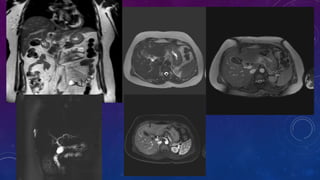

CYSTIC RENAL DISEASE

LUPUS

CALCIFIED SPLENIC GRANULOMAS

• Other than granuloma think of other causes for

liver and spleen calcifications.

• Evaluate chart for any treated lymphoma as in this

case here.

SPOT 3 ORGANS

WITH

CALCIFICATIONS

Gall stone

Calcific pancreatiits

Penile calcification